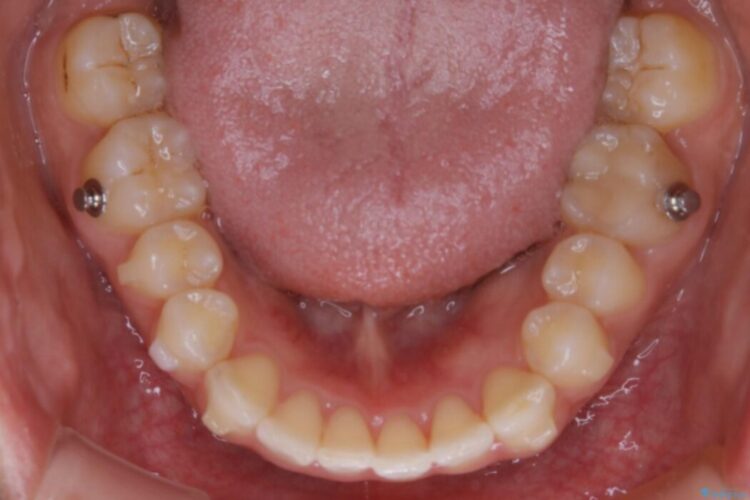

下顎前歯のガタつきを気にされて来院されました。

叢生の度合いにより抜歯は不要と判断しましたので、歯列幅の拡大を主軸に置き矯正治療を行いました。

本症例では下顎の歯列が舌側へ傾くことにより幅が狭まっていましたので、マウスピース治療により歯列弓を拡大しました。